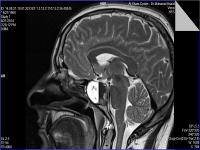

Medical imaging is an important investigative tool will help doctors to reach for the diagnosis of certain diseases, and the the advanced and high-quality imaging technologies are an important factor in maintaining the health of patients and accurate diagnosis of pathological lesions.